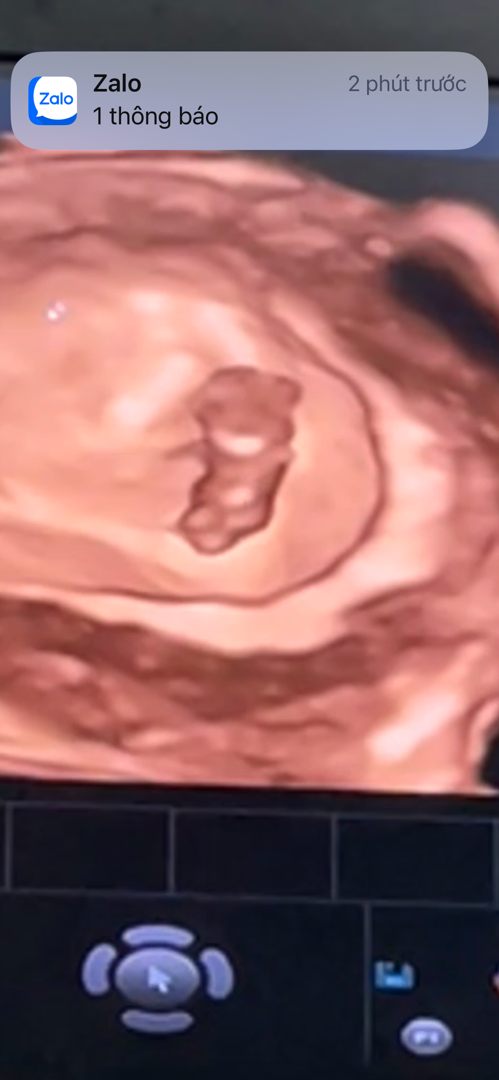

Nay mình mới đi làm Nipt , embe 10w2 đây ạ nằm tướng ghét không ạ

Dự sinh 20/08 nè , c làm ở bv tuỳ nhu cầu mình chọn gói xn thui nè , bs tư vấn kỹ theo túi tiền của mình thui nè

Mới làm hôm qua kết quả pải 10 - 14 ngày mới có á